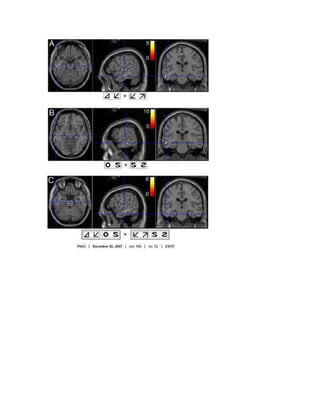

Ultrasonido normal a las 17 semanas de gestación. El cerebro y el sistema

nervioso comienzan a desarrollarse con prontitud en la vida del feto. Al realizar

un ultrasonido, el técnico por lo general busca la presencia de los ventrículos

cerebrales, los cuales son los espacios llenos de líquido en el interior del

cerebro. En este ultrasonido los ventrículos pueden observarse en la parte

superior derecha en forma de líneas finas que se extienden a través del

cráneo. La cruz apunta hacia la parte frontal del cráneo y a su derecha se

pueden observar las líneas de los ventrículos.